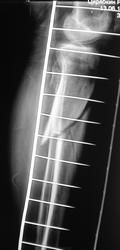

- https://radiomed.ru/sites/default/files/styles/case_slider_image/public/user/12/15.p2070032.jpg?itok=Dzc3-6js

красиво!!! DHSку теперь придется убрать, а вот что поставить? Ну может PFN, интрамедуллярный стержень с дополнительной фиксацией шейки. С б/берцовой проще, перелом благодатен для интрамедуллярного остеосинтеза.